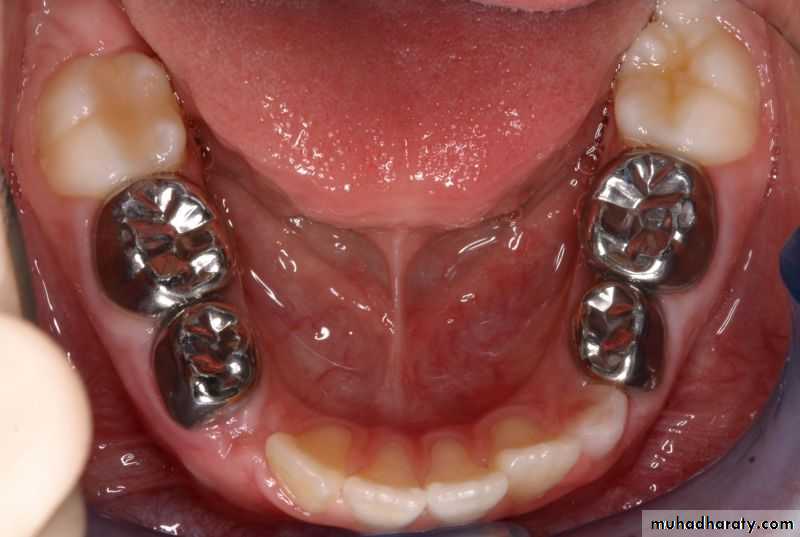

Prominent buccal cervical ridge of mand. First molar provide resistance to the placement of crowns . So it requires more reduction .Clinical significance of teeth morphology

In situations in which permanent successors of ankylosed primary molars are missing, attempts have been made to establish functional occlusion using stainless steel crowns, overlays, or bonded composite resins on the affected primary molars.